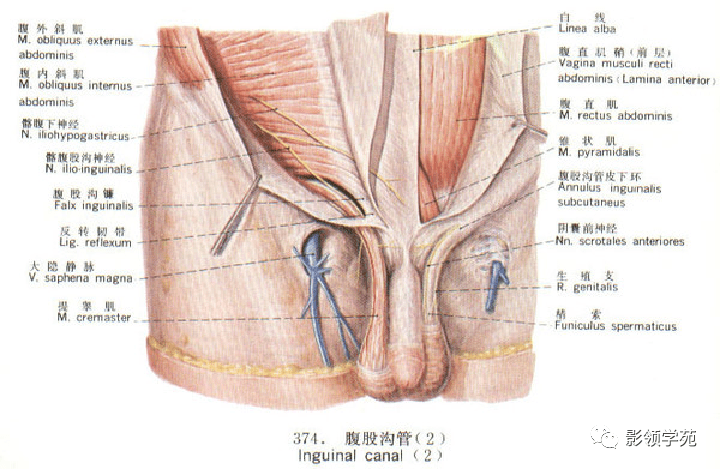

心血管系统

心血管系统